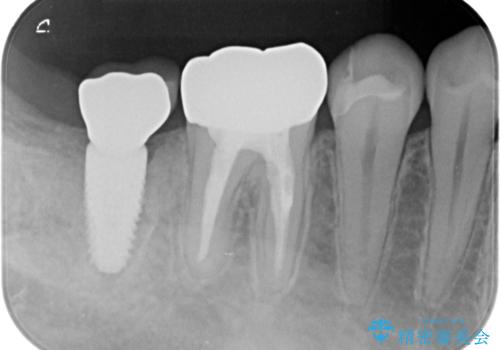

- 右下7/インプラント242,000円+アバットメント110,000円+インプラント用仮歯22,000円+ジルコニアクラウン(スタンダード)121,000円 合計495,000円(税込)費用は治療当時の料金となります

今回はかぶせ物の高さを確保するために、少し顎骨を削り、歯肉の厚みも薄くしました。